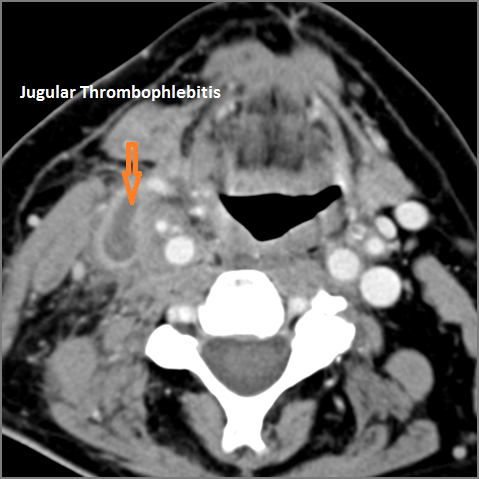

There is evidence of thrombus, thrombophlebitis or other occlusive or inflammatory process of the jugular vein or smaller venous tributaries. |

No | NA |